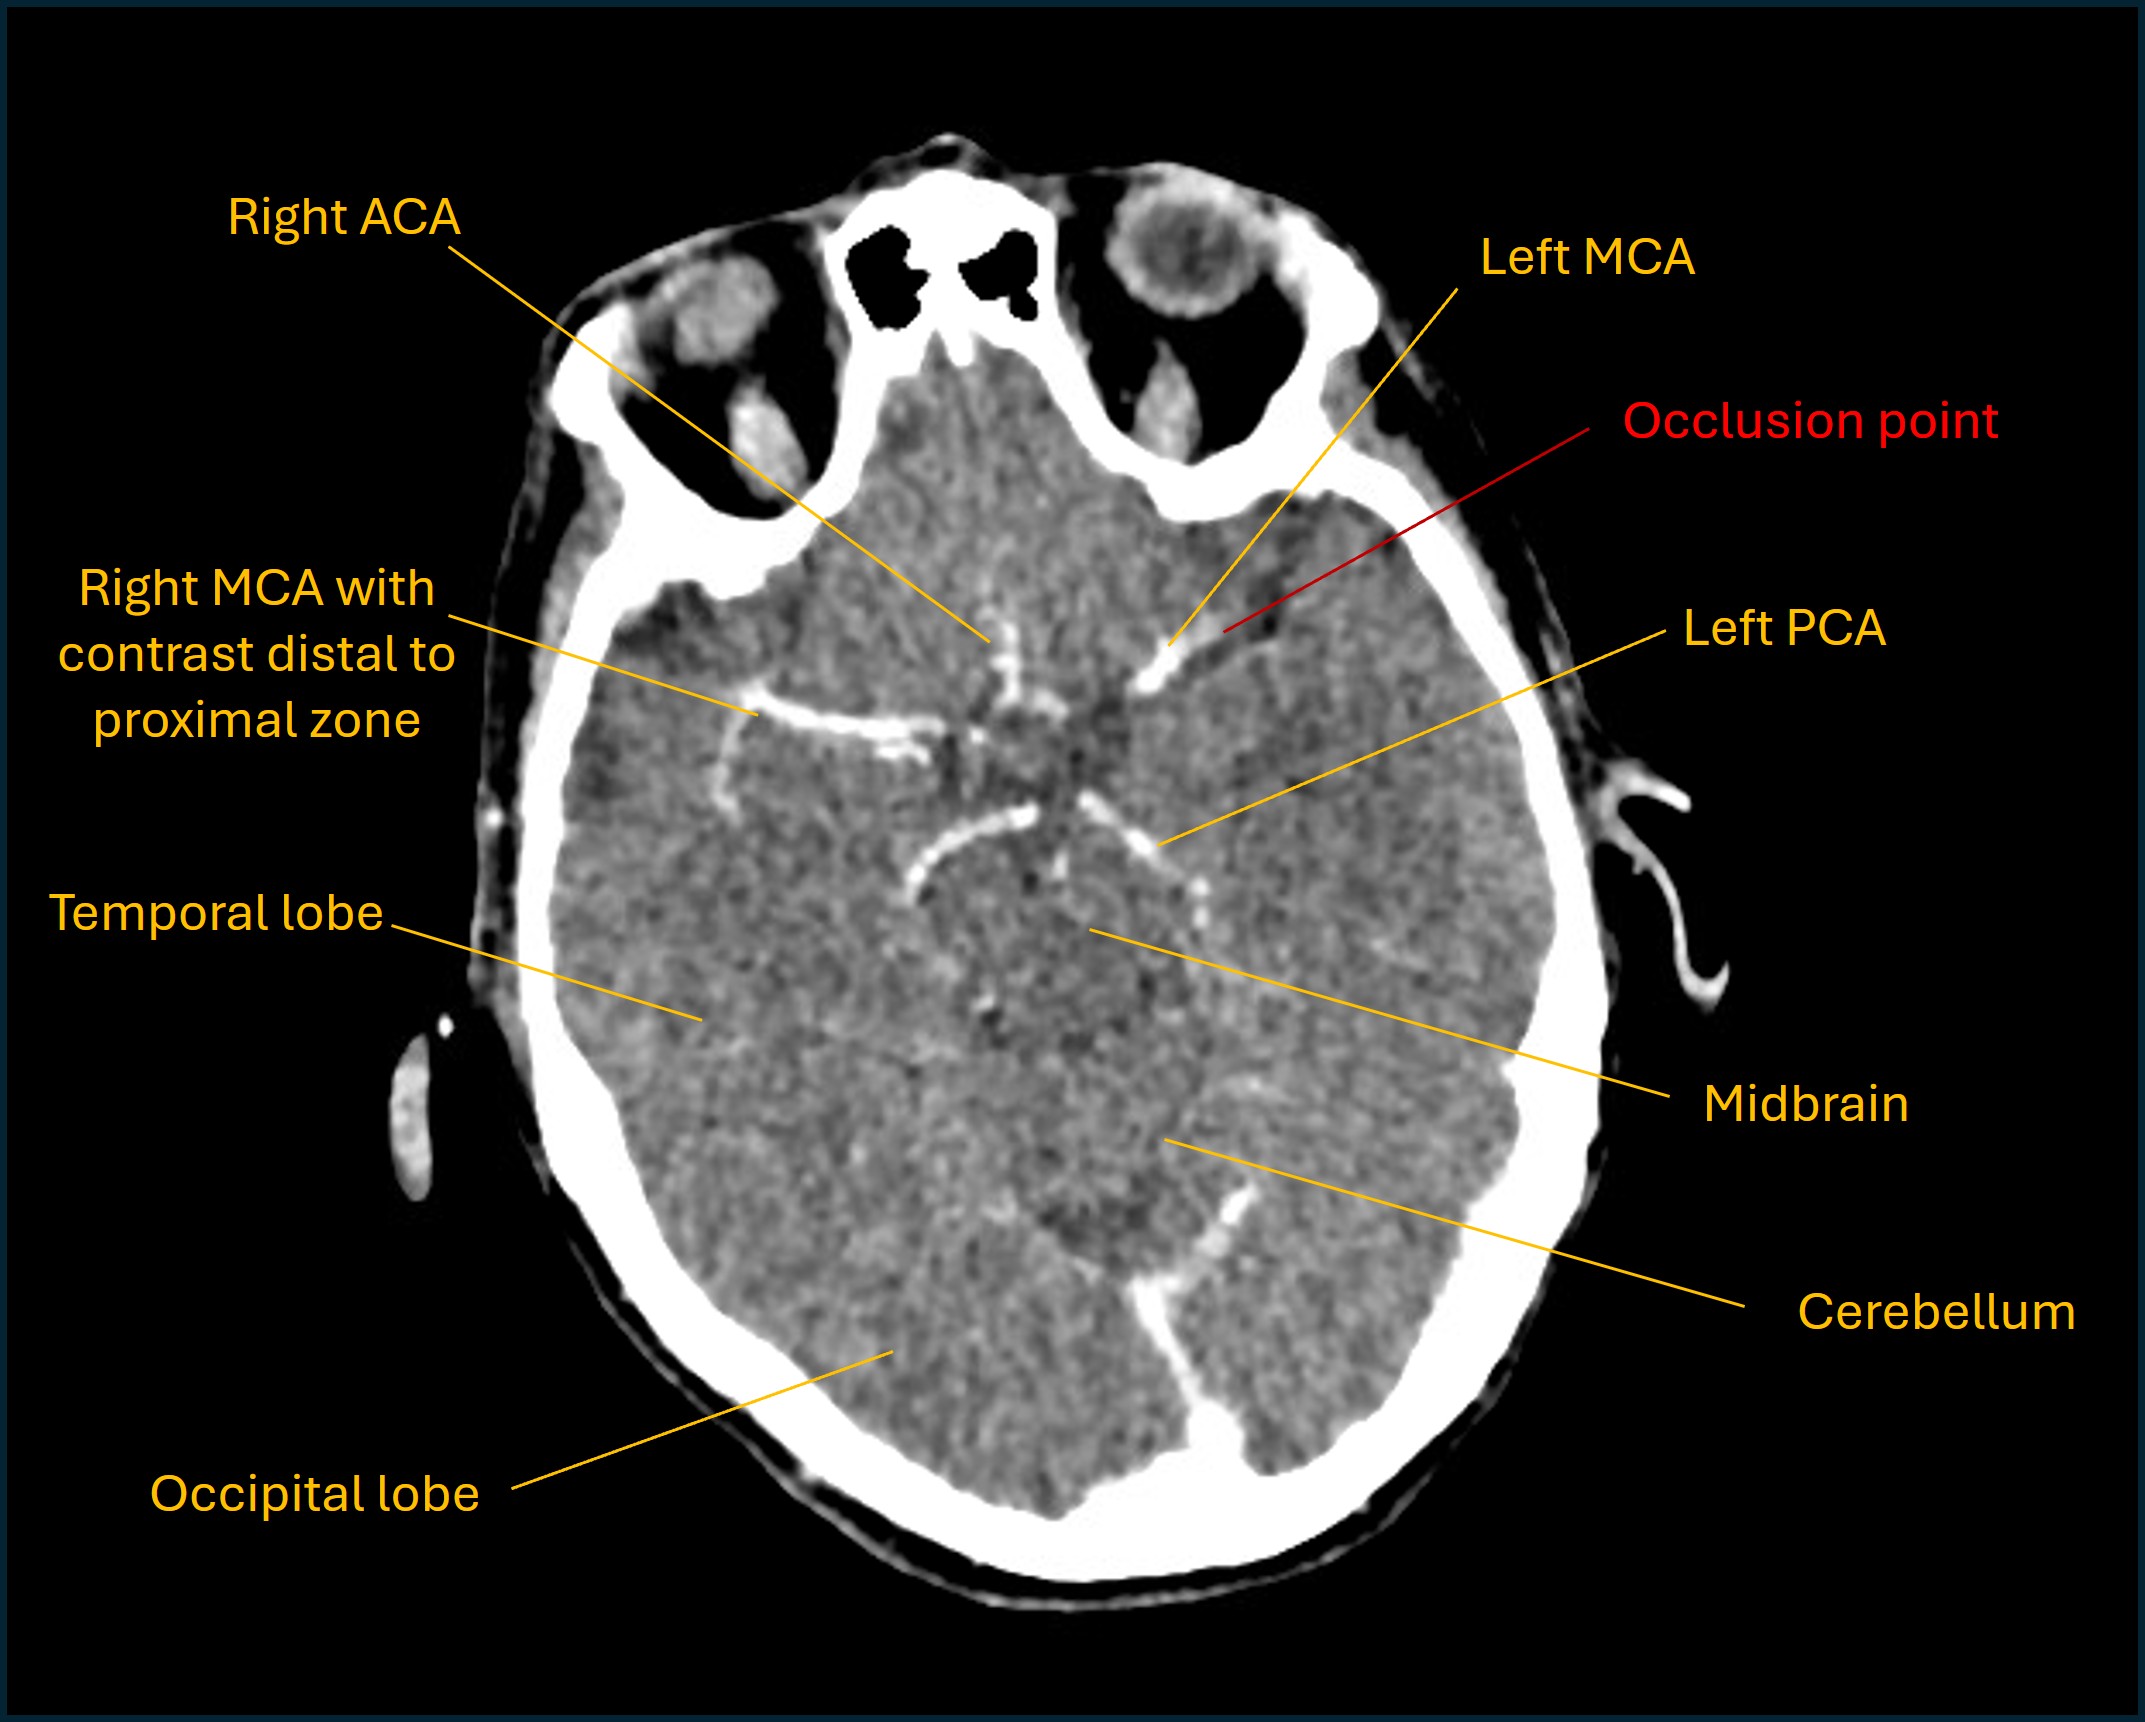

CT imaging showed no signs of acute haemorrhage. There were changes consistent with early ischaemic changes in the left hemisphere in the MCA territory, with subtle loss of grey-white matter differentiation around the insular territory, as well as hyperattentuation in the left MCA, suggestive of an occlusive thrombus.

This was confirmed on CT angiography, with occlusive thrombus sitting in the distal M1 segment of the MCA, all the way to its bifurcation into superior and inferior segments in the Sylvian fissure.